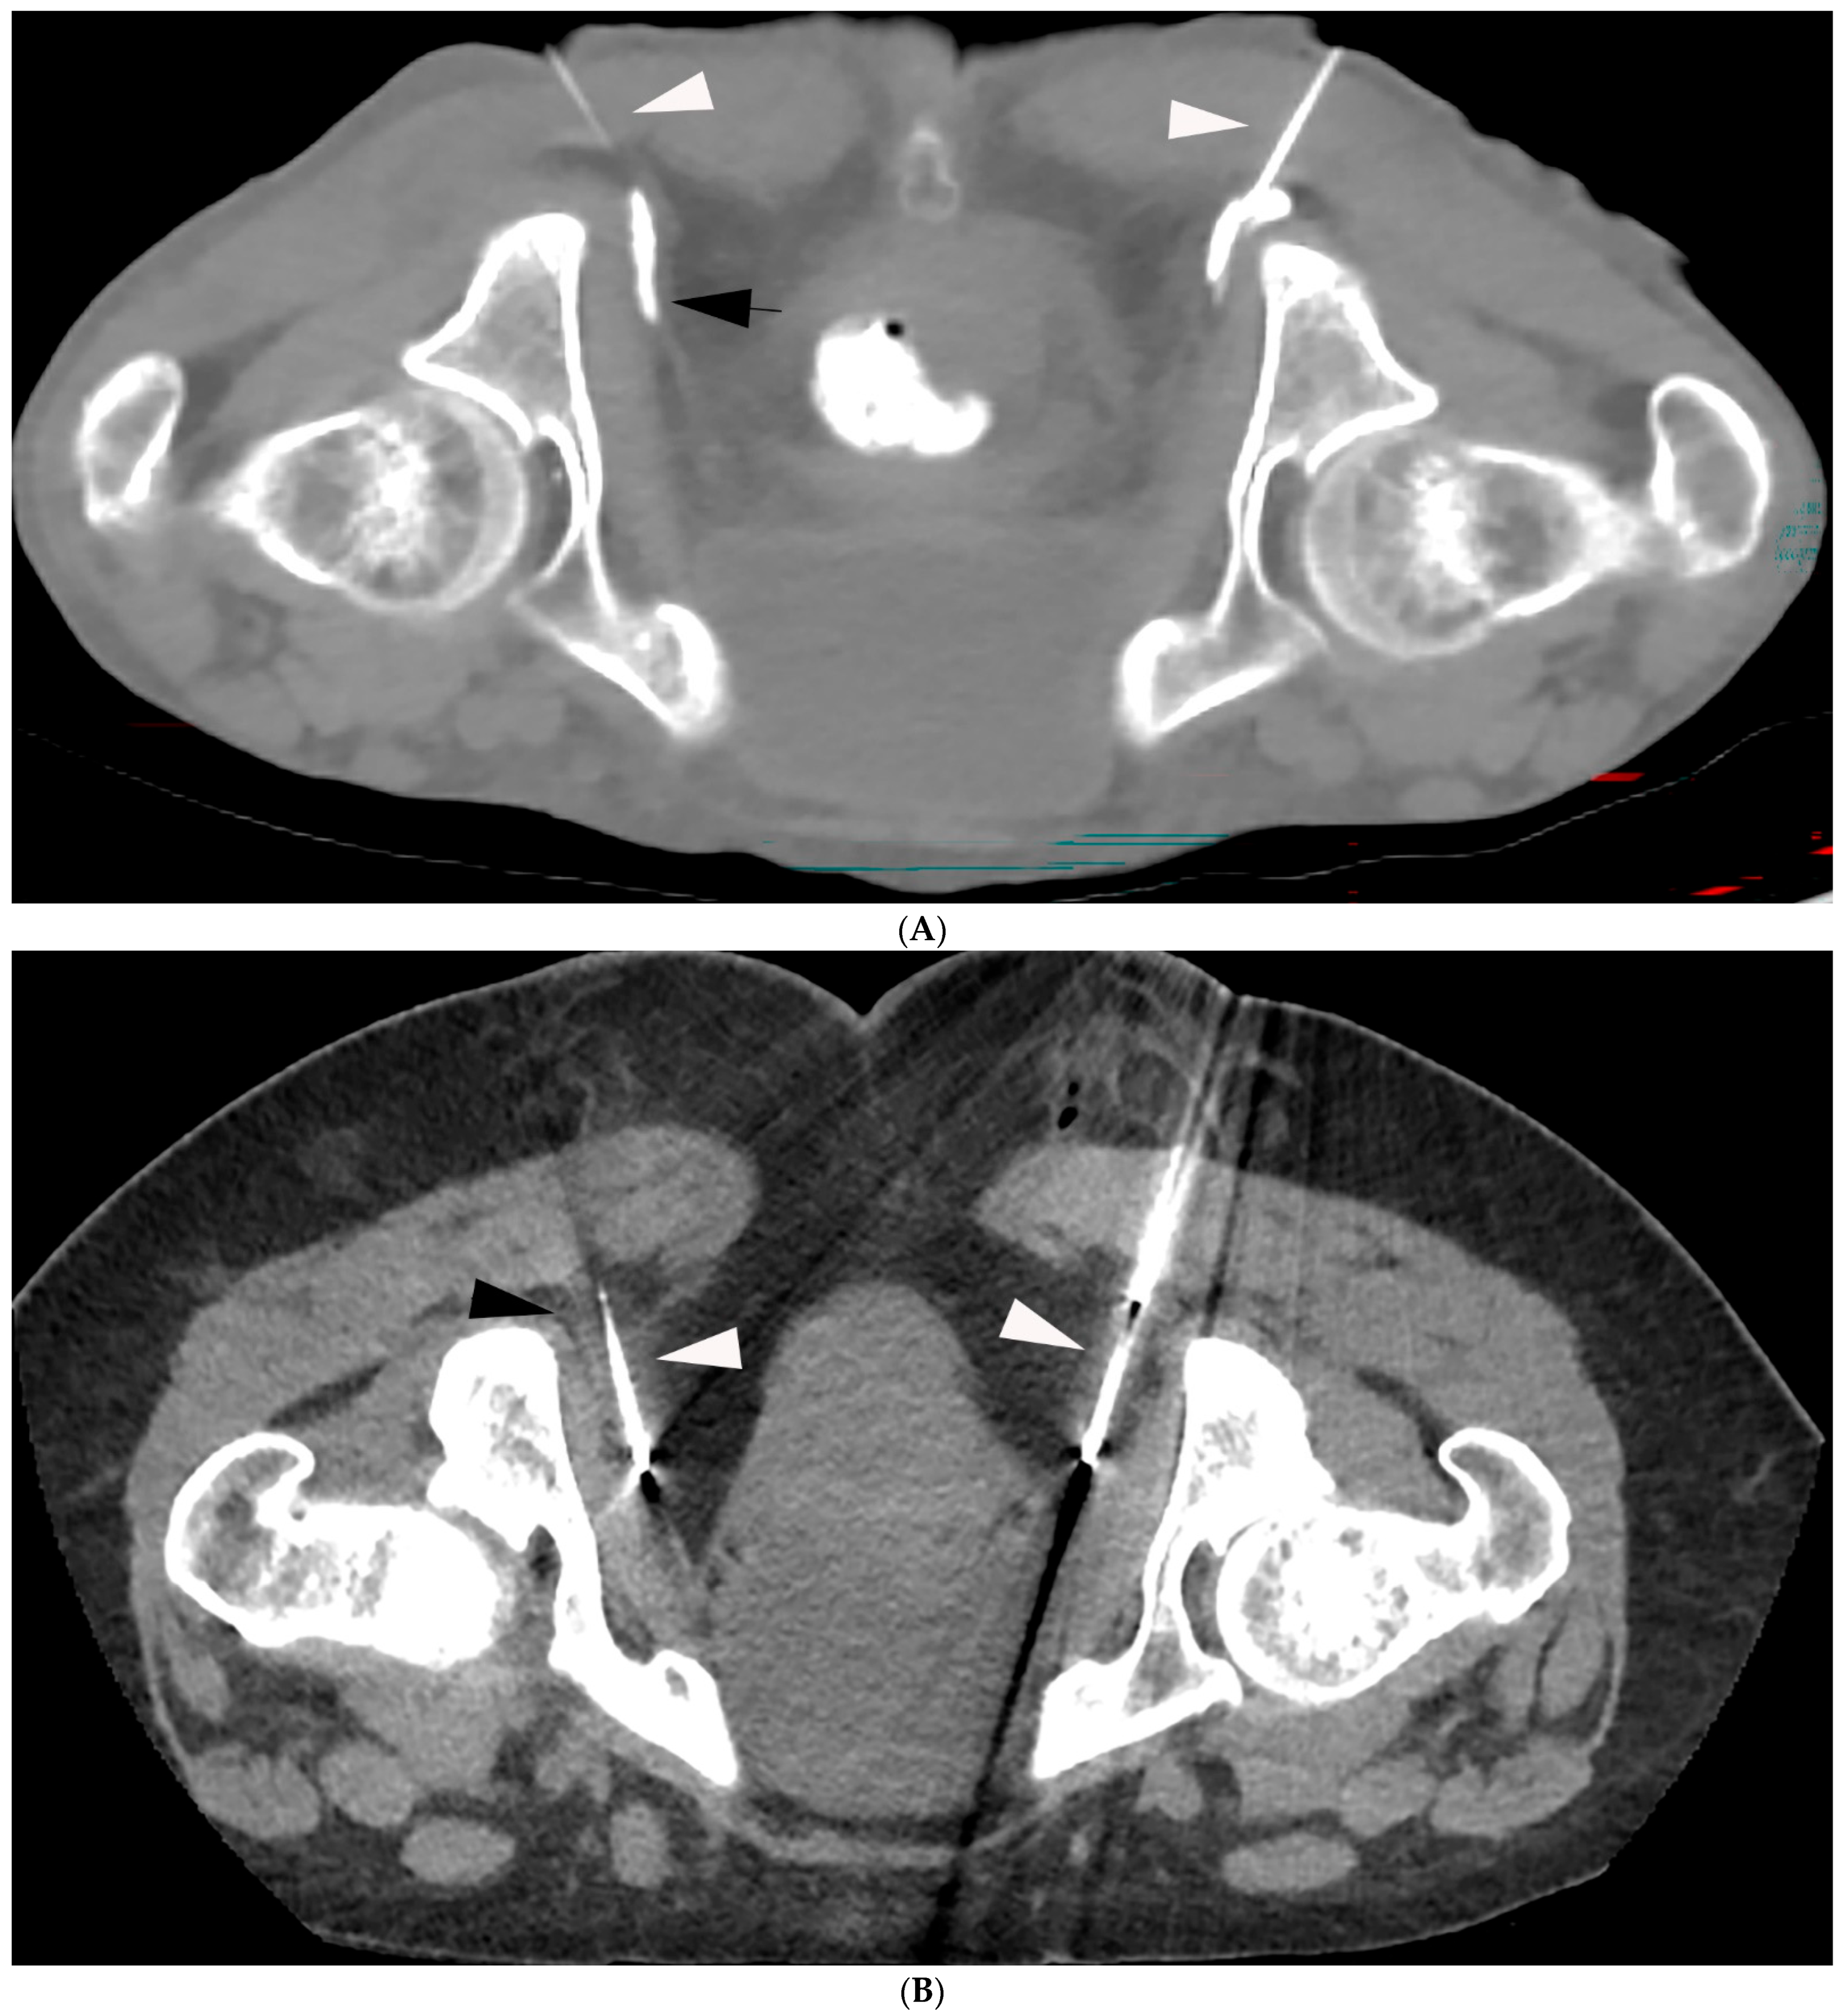

- Prologo, J.D.; Manyapu, S.; Bercu, Z.L.; Mittal, A.; Mitchell, J.W. Percutaneous CT-Guided Cryoablation of the Bilateral Pudendal Nerves for Palliation of Intractable Pain Related to Pelvic Neoplasms. Am. J. Hosp. Palliat. Care 2020, 37, 619–623. [Google Scholar] [CrossRef] [PubMed]

- Prologo, J.D.; Lin, R.C.; Williams, R.; Corn, D. Percutaneous CT-guided cryoablation for the treatment of refractory pudendal neuralgia. Skeletal Radiol. 2015, 44, 709–714. [Google Scholar] [CrossRef]